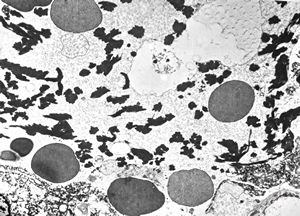

M,50y. | Pneumocystis carinii - lung